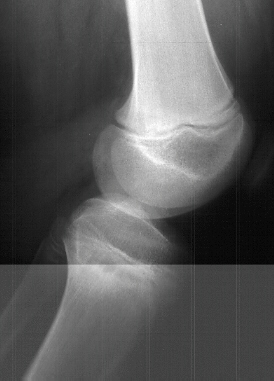

The

leg length difference with shortness makes this an ideal place

to use combined distraction lengthening and correction of deformity.